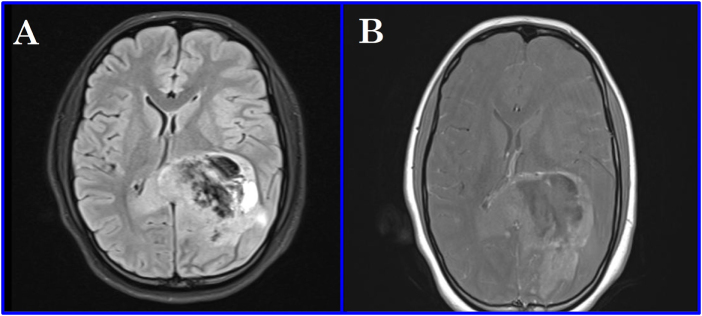

Introduction and importance: Postoperative cyst formation is a rare but significant complication following central nervous system (CNS) tumor resection. This case report describes a 14-year-old girl who developed a postoperative cyst after glioma excision, successfully managed through a minimally invasive approach.

Case presentation: A 14-year-old female presented with headache and seizures. Magnetic Resonance Imaging (MRI) revealed a mass in the trigonal region. She underwent surgical resection of the tumor. On postoperative day 7, she developed a symptomatic cyst at the tumor bed. The cyst was drained, resulting in symptomatic improvement. Follow-up assessments confirmed her clinical recovery.